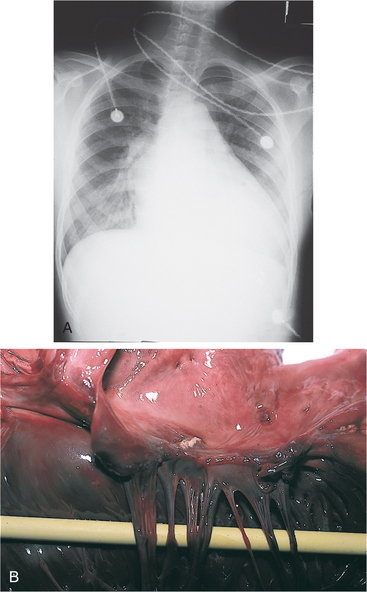

Surgical intervention may include CABG (see Fig. 12-4) for underlying myocardial ischemia and infarction; reconstruction of incompetent heart valves; ventricular remodeling or heart reduction (e.g., Batista procedure, in which a piece of the heart tissue is removed and the heart muscle is sutured back together, making a smaller, tauter heart with a stronger heartbeat); internal counterpulsation (Fig. 12-14) or external counterpulsation, which uses an external pump or balloon to adjust the aortic blood pressure; temporary ventricular assistive devices for people unable to come off bypass (see Chapter 21); and use of an artificial heart or cardiac transplantation.

Figure 12-14 The intraaortic balloon pump (IABP) is a common type of cardiac assist device that is used to improve myocardial oxygen supply-demand for individuals with deteriorating hemodynamics or ongoing ischemia, as evidenced by rest pain or electrocardiographic changes in the region of the infarct. The primary functions of balloon counterpulsation are to reperfuse the coronary arteries at the end of systole and reduce the left ventricular afterload (the amount of work the ventricle must do), thereby decreasing myocardial oxygen consumption and improving cardiac output. These intravascular catheter-mounted counterpulsation devices are traditionally used for cases of cardiogenic shock following cardiac surgery or an acute myocardial infarction as well as for people who have chronic end-stage heart failure and who are not candidates for long-term ventricular assistive device (VAD) support. The rationale for IABP counterpulsation in this latter situation is to maintain systemic perfusion and preserve end-organ function until cardiac transplantation occurs. A, The catheter is usually placed through the femoral artery, and the balloon is moved up the iliac artery to the descending aorta, where it is then placed, B, above the renal arteries and below the subclavian artery. This position is critical in order to prevent ischemia to the upper extremities or kidneys. C, When the heart contracts (systole), the balloon is deflated, creating a decline in aortic pressure. After the heart contracts (during diastole), the balloon is filled with air, causing the blood to regurgitate back toward the root of the aorta, thereby perfusing the coronary arteries. When the left ventricle is ready to pump, the balloon is deflated (cardiac systole again), reducing ventricular afterload. (A, courtesy Chris Wells, PT, MS, PhD, University of Pittsburgh Medical Center, 2001. B, from Black JM, Hawks JH, Keene AM: Medical-surgical nursing: clinical management for positive outcomes, ed 7, Philadelphia, 2005, Saunders. C, from Lewis SL, Heitkemper MM, Dirksen SR: Medical surgical nursing: assessment and management of surgical problems, ed 7, St Louis, 2007, Mosby.)